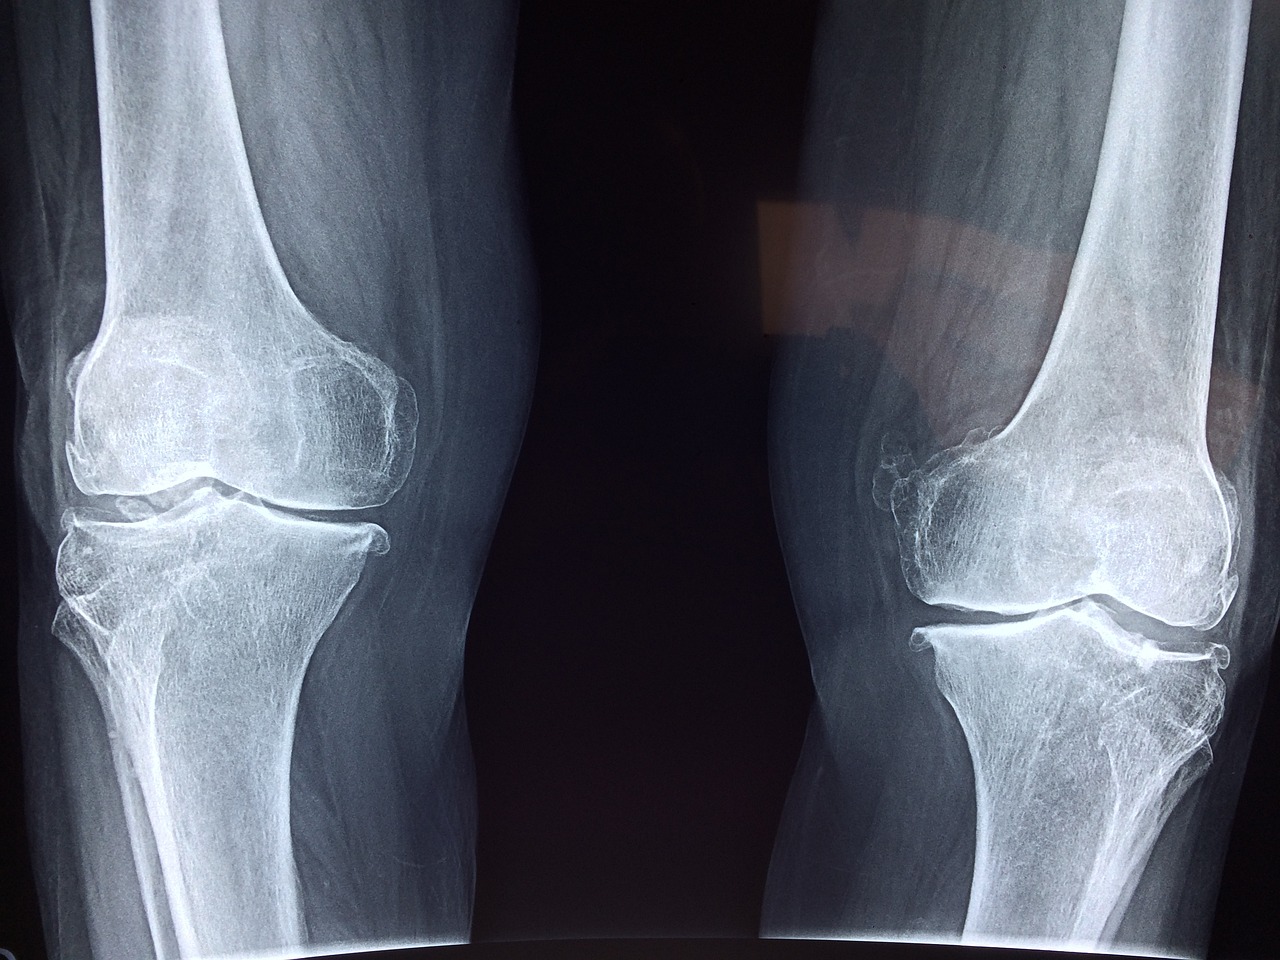

- X-ray : 무릎 관절의 구조적 이상 여부를 확인할 수 있습니다.

- MRI : 연골, 건, 인대 등의 상태를 자세히 볼 수 있어 슬개건염 진단에 도움이 됩니다.

- 초음파 : 비침습적으로 슬개건의 상태를 실시간으로 확인할 수 있습니다.